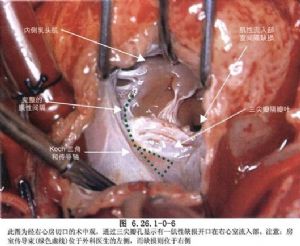

(2)右房切口:上起右心耳,下至下腔靜脈上方,平行房室溝並距離1~2cm做房壁斜切口,於切口後緣縫兩牽引縫線,注意避免損傷位於上腔靜脈與右房交界處,即界溝上方心外膜下的竇房結。將心房壁切口前緣向前牽拉即可顯露三尖瓣環,房室結位於冠狀靜脈竇口內上方即Koch三角區內。

(4)注意傳導束行徑:房室結位於缺損的後下緣肌肉部分,正對三尖瓣間隔瓣和前瓣交界的心房側,希氏束在室間隔缺損後下緣處穿過,此處是手術中最容易損傷的部位(圖6.26.1-1)。

②膜周型缺損修補方法:應用補片間斷褥式縫合法:於三尖瓣環後下緣和隔瓣根部,應用間斷帶墊片褥式縫線縫合3~5針褥式縫線(圖6.26.1-3),分別穿過補片結紮,再順鐘向到後上方縫於心室漏斗褶與三尖瓣環結合處。若心室漏斗褶發育不全,在此處有時要用帶小墊褥式縫線1~2針直接縫於主動脈瓣環上,然後轉至室上嵴;下方轉移至竇部室間隔之右心室面,每針縫線均穿過補片相應部位,推下補片結紮縫線。缺損的其他部分可應用間斷帶墊片褥式縫合或連續縫合,完全閉合室間隔缺損(圖6.26.1-4)。